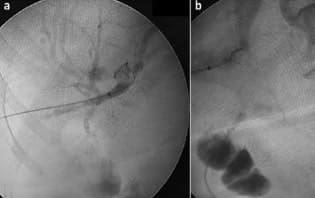

Asistimos el procedimiento vía laparoscópica, mediante punción y administración de medio de contraste en el asa intestinal (figura 1), avance de la pinza laparoscópica y captura de la guía biliar (rendezvous).

Figura 1. (a) Colangiografía transparieto-hepática derecha (instrumentación biliar percutánea). (b) Punción del asa desfuncionalizada e inyección de medio de contraste